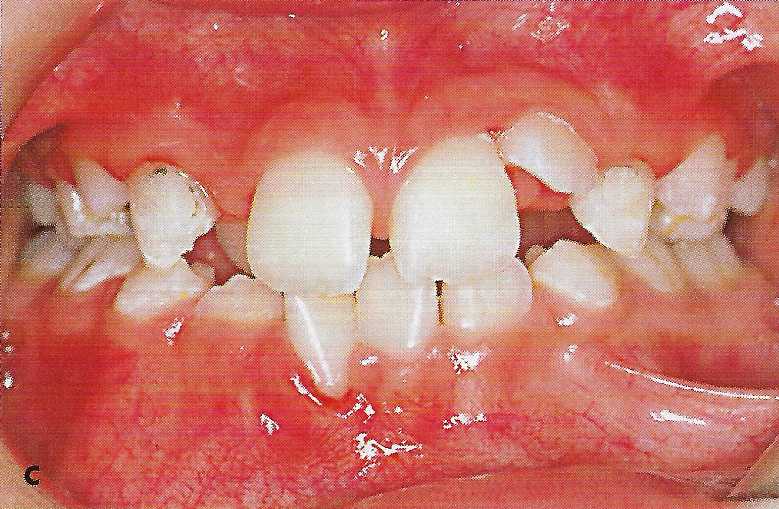

Abb. 1 a bis h Extra- und intraorale Ansicht der Patientin vor Behandlungsbeginn: Kopfbiß beziehungsweise umgekehrter Schneidezahnüberbiß und beidseitiger Kreuzbiß als Folge einer maxillären Hypoplasie sowie hälftenungleicher Mesialbiß infolge mandibulärer Verschiebung nach rechts.

• Ankylose Abb.1c

Diese Patientin war zu Behandlungsbeginn 7 Jahre alt. Sie hatte einen hälftenungleichen Mesialbiß infolge mandibulärer Verschiebung mit Kopfbiß beziehungsweise umgekehrter inzisaler Stufe, rechtsseitigem vollem Kreuzbiß und linksseitigem doppeltem Höckerbiß, maxillärer Kompression sowie Platzmangel in beiden Kiefern (Abb. 1 a bis h). Die kephalometrische Analyse ergab eine progene Kieferlagebeziehung, bedingt durch eine unterentwickelte Maxilla bei vertikalem Gesichtsschädelaufbau.